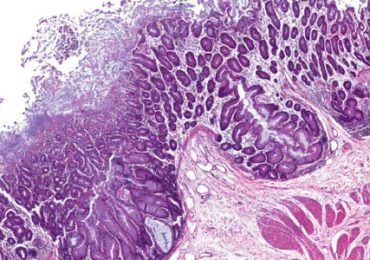

Verband tussen overtollige vetinname en pancreaskanker

Pancreaskanker is een van de meest dodelijke kankers bij de mens. Een studie op knaagdieren wees uit dat een vet- en calorierijke voeding premaligne letsels…